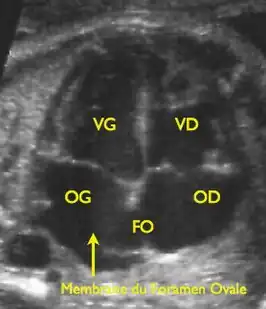

VG: linker ventricel, VD: rechter ventrikel, OG: linkeratrium, OD: rechteratrium, FO: foramen ovale